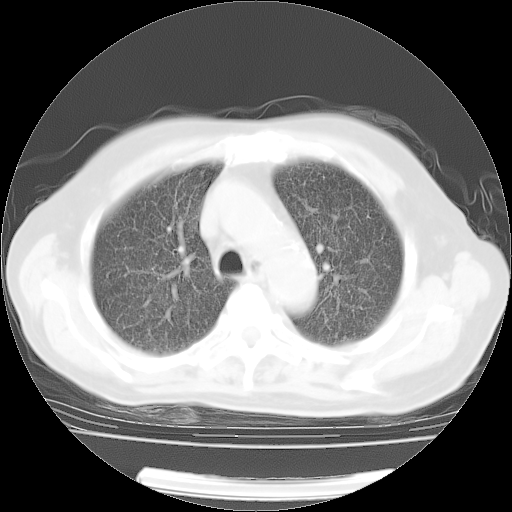

4月14日肺部CT

4月28日肺部CT——再次出现类似去年5月9日——透光度降低,(影像科认为)“间质性”改变。